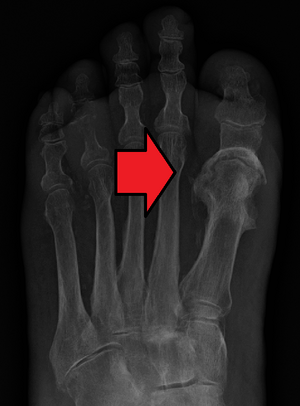

Osteomyelitis of the 1st toe | |

Diagnosis of osteomyelitis is often based on radiologic results showing a lytic center with a ring of sclerosis.[13] Culture of material taken from a bone biopsy is needed to identify the specific pathogen;[27] alternative sampling methods such as needle puncture or surface swabs are easier to perform, but cannot be trusted to produce reliable results.[28][29]